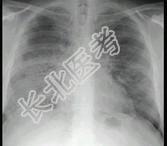

- 单项选择题24岁女性,咳嗽、进行性胸闷、气促2月, 支气管镜如图,镜下可见大量米汁样分泌物。影像学检查如图。可能的诊断是 ( )

A、肺泡蛋白沉积症